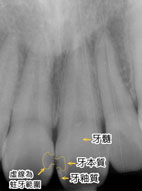

牙釉質蛀牙在牙齒表面上可以看到的是細小的黑色凹槽。當蛀牙穿過牙釉質進入牙本質,細菌會沿著牙本質小管侵入並擴大感染面積(如:圖一)。當蛀洞位在牙縫(牙齒鄰接面)無法直接肉眼辨識時,便須借助X光片的影像來檢查是否有牙縫間蛀牙。

圖一

由圖片(如:圖二、圖三)所示可知,若蛀牙侵犯到牙本質的層級時,即便牙齒表面看起來沒有很大的缺損,但其實在牙釉質底下已經埋藏了一個大蛀洞了。